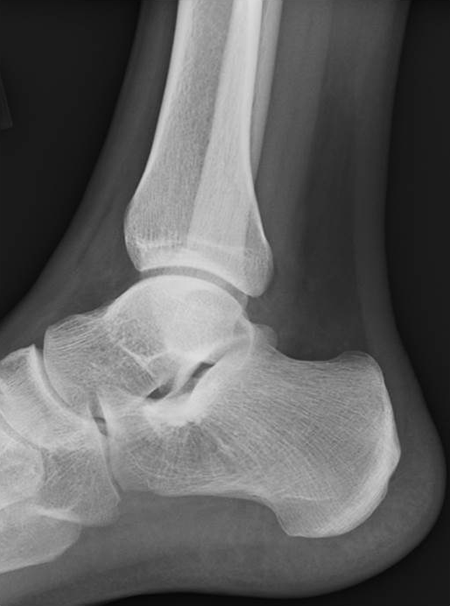

Hematological tests showed pancytopenia (Table 1). X-ray and computed tomography (CT) showed no evidence of destruction of the trabeculae in the left calcaneus (Figure 1 and Figure 2A,B). However, on MRI, the middle to posterior part of the left calcaneus showed low intensity in T1-weighted image, high intensity in T2-weighted image, and high intensity in short-TI inversion recovery (Figure 3A-C). Taking all clinical physical findings into consideration, we suspected that the lesion of the left calcaneus was either a lymphoproliferative tumor, such as leukemia, multiple myeloma, or lymphoma, or a trabecular type bone metastatic tumor, such as small cell carcinoma.

Lateral x-ray shows no trabecular bone destruction.